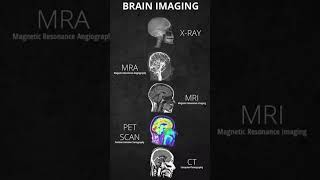

The X Ray Imaging System (A) Brain imaging||Xray, MRA, CT scan, PET scan, MRI #brain #medical #xray

Brain imaging||Xray, MRA, CT scan, PET scan, MRI #brain #medical #xray Xray PNS sinusitis #anatomy #xraytechnician #humananatomy #radiologycareer #doctor #xray #humanbody

The X Ray Imaging System (A) Brain imaging||Xray, MRA, CT scan, PET scan, MRI #brain #medical #xray

Brain imaging||Xray, MRA, CT scan, PET scan, MRI #brain #medical #xray Xray PNS sinusitis #anatomy #xraytechnician #humananatomy #radiologycareer #doctor #xray #humanbody